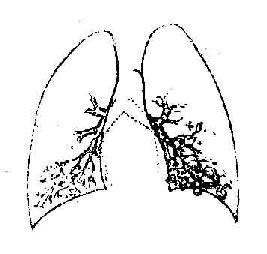

(二)支气管造影

正常支气管显示规则的树枝状,逐渐分支,越分越细,管壁光滑整齐。支气管扩张的造影所见可分为柱状、囊状及混合型三种类型。柱状支气管扩张表现为管腔呈圆形或杵状,远端稍大。并发肺不张时,扩张的支气管可有聚拢现象。囊状支气管扩张表现为支气管未端呈多个扩张的囊,状如一串葡萄(图3-17A,B)。造影剂常部分充盈囊腔,在囊内形成液面状与囊状同时并存,是为混合型,病变往往比较明显而广泛。

图3-17A 左下囊状支气管扩张支气管造影所见